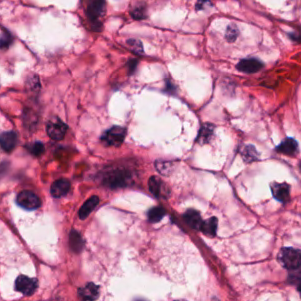

As an essential part of digital pathology, histopathology image analysis is playing increasingly important role in cancer diagnosis, which can provide direct and reliable evidence to diagnose the grade and type of cancer. This paper deals with nuclei segmentation, an important step in histopathological image analysis. The purpose of nuclei semgentation is not only counting the number of nuclei but also obtaining the detailed information of each nucleus. So unlike nuclei detection, here the outputs are the contour of each nucleus instead of only the position of their central points. Hence we can exactly extract each nucleus from the image and make it available for further analysis. For example, the features of the individual nucleus and the distribution of nuclei clusters can be used to grade and classify status of breast cancers [3, 4]. Because of appearance variation such as color, shape, and texture, nuclei segmentation from histopathological images could be very challenging, as illustrated in Fig.1, in which it is very challenging even for human to recognize and segment all nuclei within the images. Fig.1(a) and Fig.1(b) illustrate two histopathological images from different organs. Fig.1(c) and Fig.1(d) are two histopathological images from same organ but have different cancer grade.

H&E stain is the most widely used stain protocol in medical diagnosis. Typically, the nuclei of cells are stained to blue by Haematoxylin while cytoplasm is colored to pink by Eosin. But in practice, the color of H&E stained images could vary a lot due to variation in the H&E reagents, staining process, scanner and the specialist who performs the staining, as shown in Fig.1. A few H&E stain normalization methods[23, 24, 25] have been proposed to eliminate the negative interference caused by color variation. We tried two of them[23, 25] to normalize the raw H&E stained images. For our segmentation algorithm, we did not find any considerable difference between these two normalization methods. Particularly, the result shown in experiment section III is generated based on the images normalized by the method in [23]. Given a target image, this method is able to convert one image’s color into the target image’s color space based on sparse non-negative matrix factorization(NMF). We choose one best stained H&E image as the target and convert other images into its color space. According to the recommendation in [23], the hyper-parameter should be set between 0.01 and 0.1. In our experiment, is set to 0.1.

Figure 6 shows how our method segments the nuclei step by step. The color variety is well controlled by the color normalization procedure. The prediction result shows clear nuclear areas and nucleus boundaries. In the final segmentation result and ground truth image, each nucleus is represented by a different color.